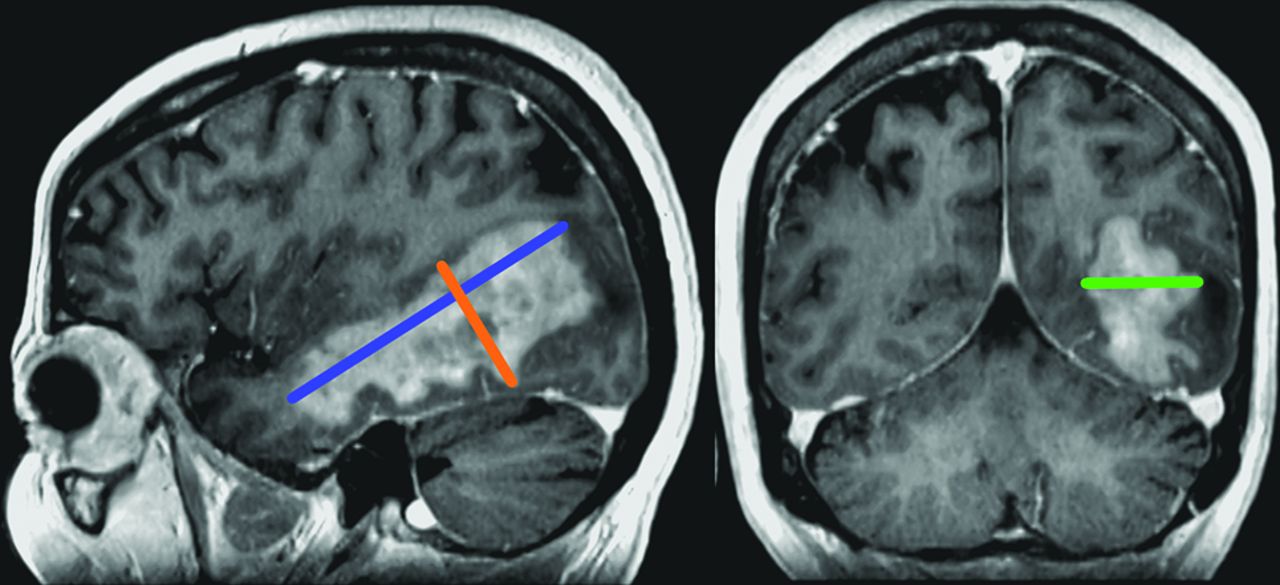

The longest 1D measurement was the sum of the longest diameters of all enhancing lesions among the measurements obtained on axial, coronal, or sagittal planes (Fig 1, blue line). In other words, the longest 1D measurements were made by adding the length of each lesion’s longest axis. The longest 1D measurements were expressed in millimeters.

3D measurement example on postcontrast 3D T1 MPRAGE. The blue line represents the longest 1D. The orange line is the longest length perpendicular to the blue line; their product represents 2D. The green line is the longest length perpendicular to the blue and orange lines; those 3 measures are used to calculate the volume for 3D.

The 2D measurements corresponded to the sum of the products of the longest length of enhancing lesions with their maximum perpendicular diameter obtained in the same plane (axial, coronal, or sagittal) (Fig 1, orange line). 2D measures were expressed in square millimeters.

The 3D volumes were calculated using the 2 lengths obtained for calculating the 2D measurements and the longest perpendicular diameter (Fig 1, green line). The volume of each lesion was estimated by an ellipsoid formula [V = (4×π×A × B × C) / 3] and expressed in cubic millimeters. If there was >1 lesion, 3D measurements corresponded to the summation of the different volumes.